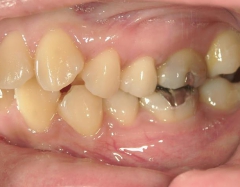

矯正歯科 治療前